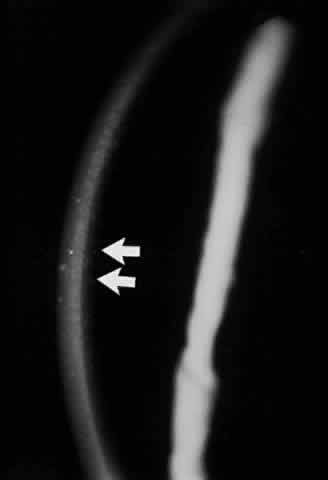

There is considerable evidence to support the concept that primary corneal and conjunctival changes occur in ichthyosis. In a series of 62 patients reported by Jay and co-workers, 16 patients had characteristic corneal changes.172 Of these, 13 had sex-linked ichthyosis and 3 had ichthyosis vulgaris. None of these patients had lamellar ichthyosis, the form most frequently complicated by ectropion. Sever and his colleagues also noted corneal changes only in male patients with X-linked ichthyosis.171 These opacities were diffuse and confined to one deep layer of the cornea, either Descemet's membrane or deep stroma. The opacities were dot or filament shaped (Fig. 23). The opacities became more apparent with increasing age and were not associated with any visual loss. None of the patients with lamellar ichthyosis showed this change, but it was present in most of the female carriers of X-linked ichthyosis. Katowitz and his co-workers have reported the primary involvement of conjunctiva in ichthyosis, citing keratinization, hyperkeratosis, parakeratosis, and papilla formation as characteristic histologic features.175 Because their biopsy material was taken from the fornix region, these authors believed that the observed changes were primary in nature and not due to exposure, as others have suggested.

Fig. 23. Corneal opacities in a patient with X-linked icthyosis.